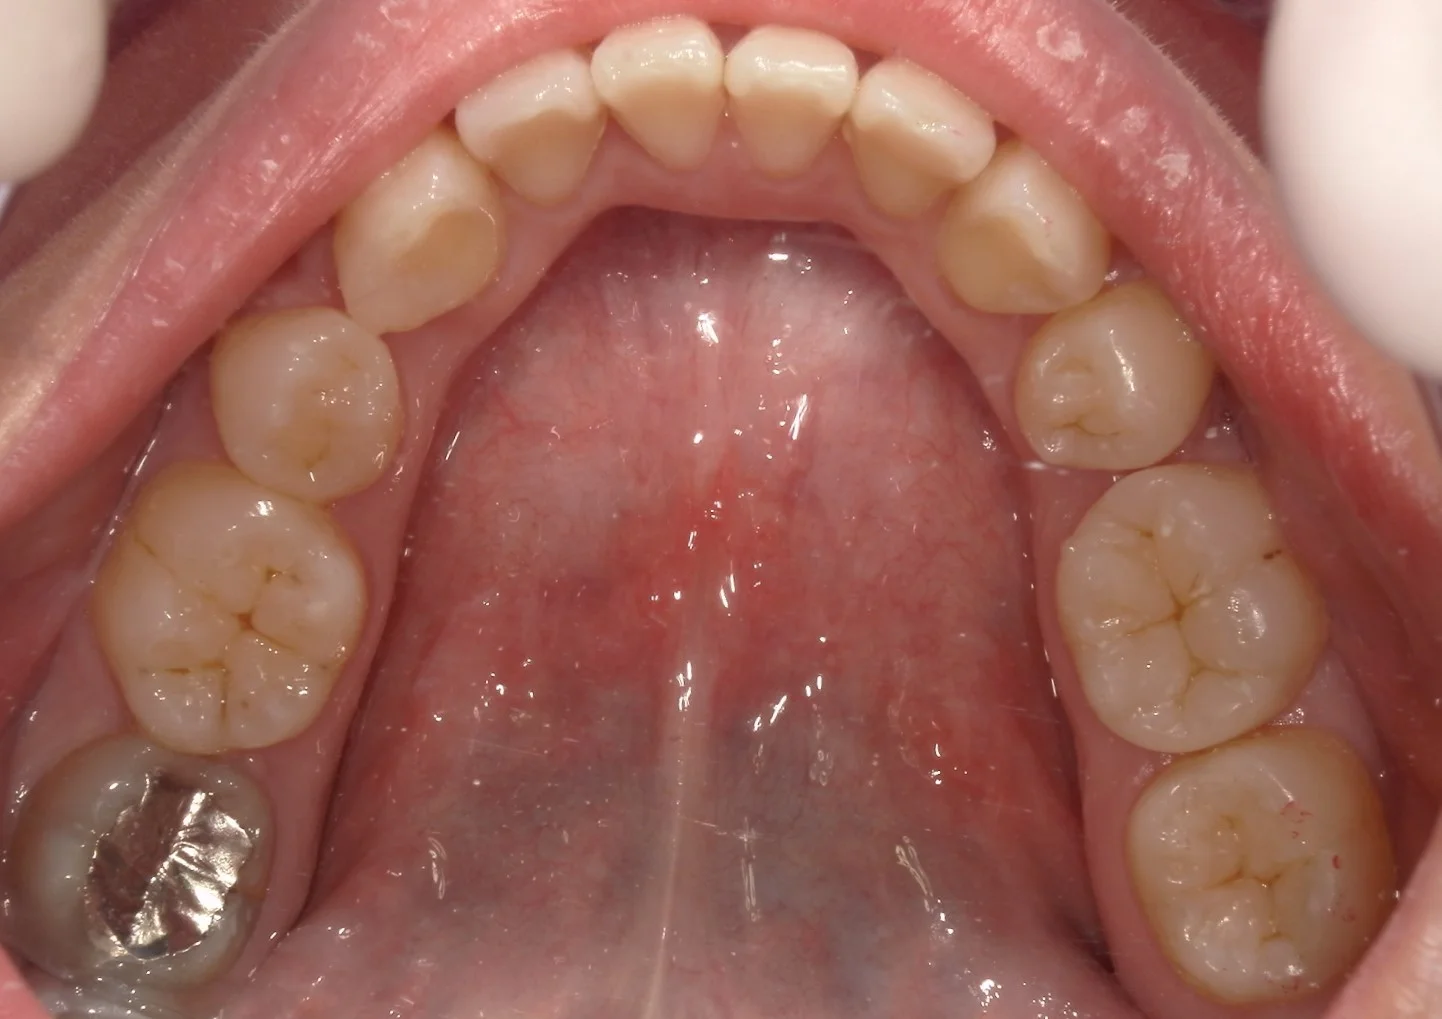

さて、この上下の歯のどこをどこを治療したでしょうか・・・!!

正解は下の方で・・・!